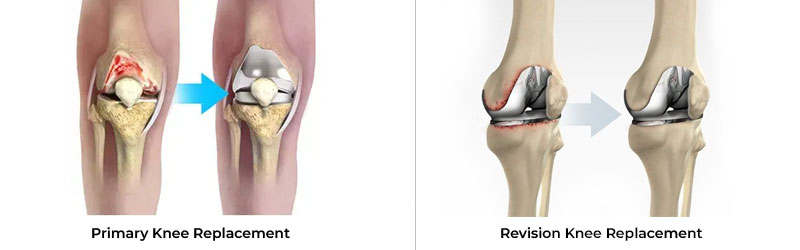

Primary Knee Replacement and Revision Knee Replacement are surgical procedures related to the knee joint, commonly performed to relieve pain and restore function in patients with severe arthritis or knee damage.

Primary knee replacement is the first surgery a patient undergoes to replace a damaged or worn-out knee joint. It is typically performed for conditions like osteoarthritis, rheumatoid arthritis, or traumatic injury to the knee joint.

Revision knee replacement is a more complex procedure done when a previously implanted knee prosthesis fails or wears out. It involves removing the old prosthetic components and replacing them with new ones.